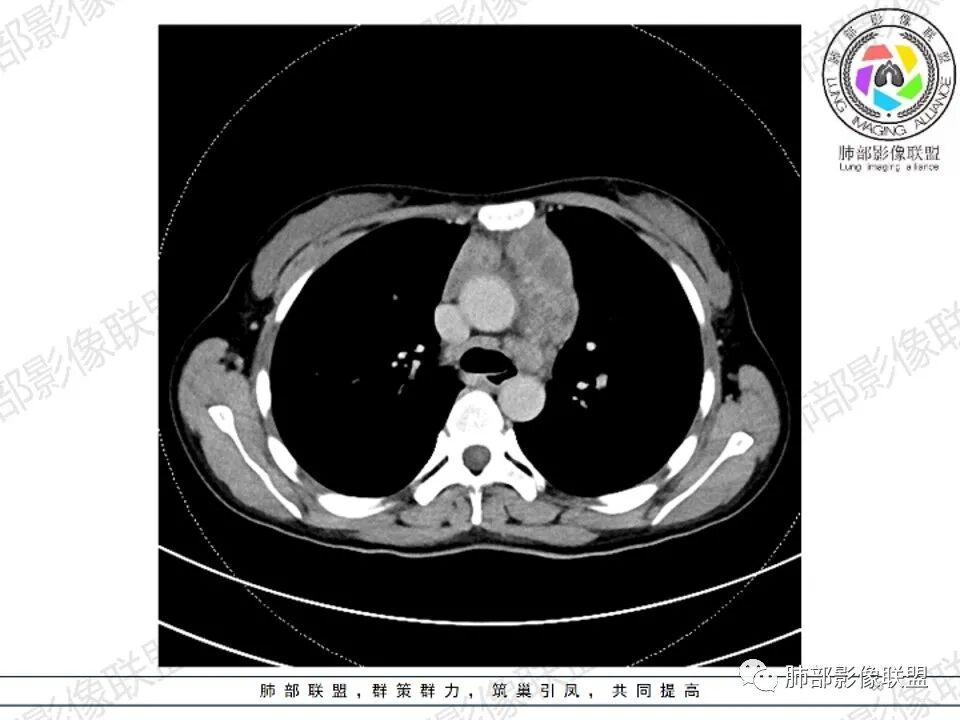

年轻女性,贫血,CT示前纵隔团片状软组织占位,多结节堆积感,塑形生长,边界欠清,包绕大血管及心包,增强明显不均匀强化,内见血管漂浮。纵隔4R,5,7区及双侧腋窝多发肿大淋巴结,综合考虑为淋巴瘤可能

前纵隔和双侧腋窝多发的淋巴结肿大,前纵隔为甚,融合呈中等强化,部分坏死呈低密度,包埋肺动脉主干和左心缘,融合斑块状,内见血管飘浮特点,前纵隔脂肪间隙混浊,首选淋巴瘤!

1.年轻女性,前纵隔不规则块状影,密度不均,边界不甚清楚,有结节融合感,轻度不均匀强化,可见血管穿行,最常见最符合的无疑是淋巴瘤!